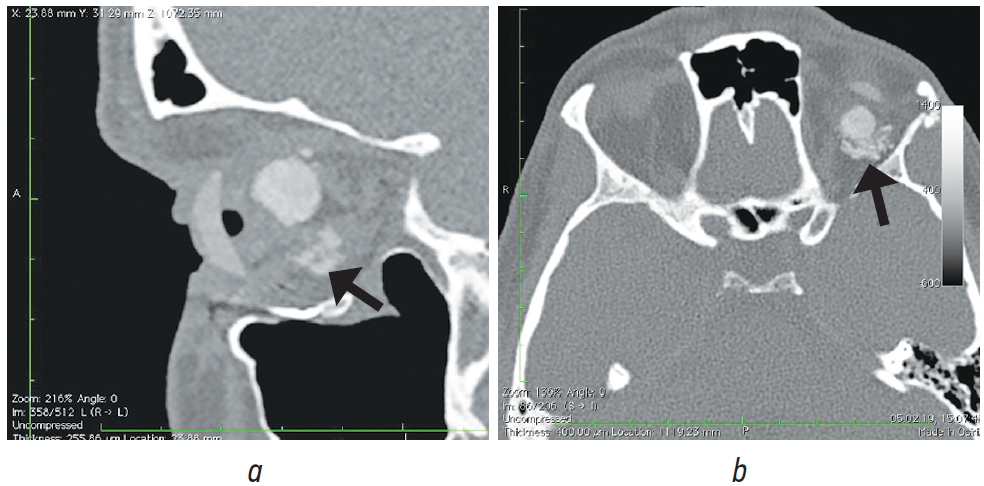

Рис. 8. Пациент, 21 год. 2,5 года после операции с имплантацией эндопротеза с изменённой геометрией. МСКТ-исследование

Fig. 8. Patient, 21 y. o. 2,5 years after surgery with implantation of an endoprosthesis with modified geometry. MSCT of the socket

При анализе рентгенологических изображений после выполнения МСКТ-диагностики у всех обследованных пациентов по описанному ранее алгоритму [16] нами было выявлено изменение размеров и геометрии орбитальных сфер в виде «срезанной» части (рис. 8). Параметры изменённой части, как и размеры самих имплантатов, были различны (табл. 1–3). Исходные параметры (диаметры) орбитальных сфер — 18, 19 и 20 мм. При компьютерно-томографическом исследовании на полученных изображениях мы анализировали размеры имплантированных материалов, определяя объём вкладышей через радиус и высоту срезанной части по формуле: V = 1/3πh2(3r – h), где π — константа, равная 3,14; r — радиус шара; h — высота шарового сегмента имплантата.

В мягких тканях вокруг изменённых имплантированных сфер нами выявлены уплотнения, без признаков кальцинации и деструкции стенок орбиты (рис. 7, 8). Кроме того, у одной пациентки было отмечено не только изменение геометрии сферы в виде срезанной части (рис. 10, а), но и наличие множества фрагментов полимерного материала идентичной рентгенологической плотности. Эти фрагменты имплантата находились за задним полюсом полимерного вкладыша в мягких тканях до вершины орбиты (рис. 10, b).